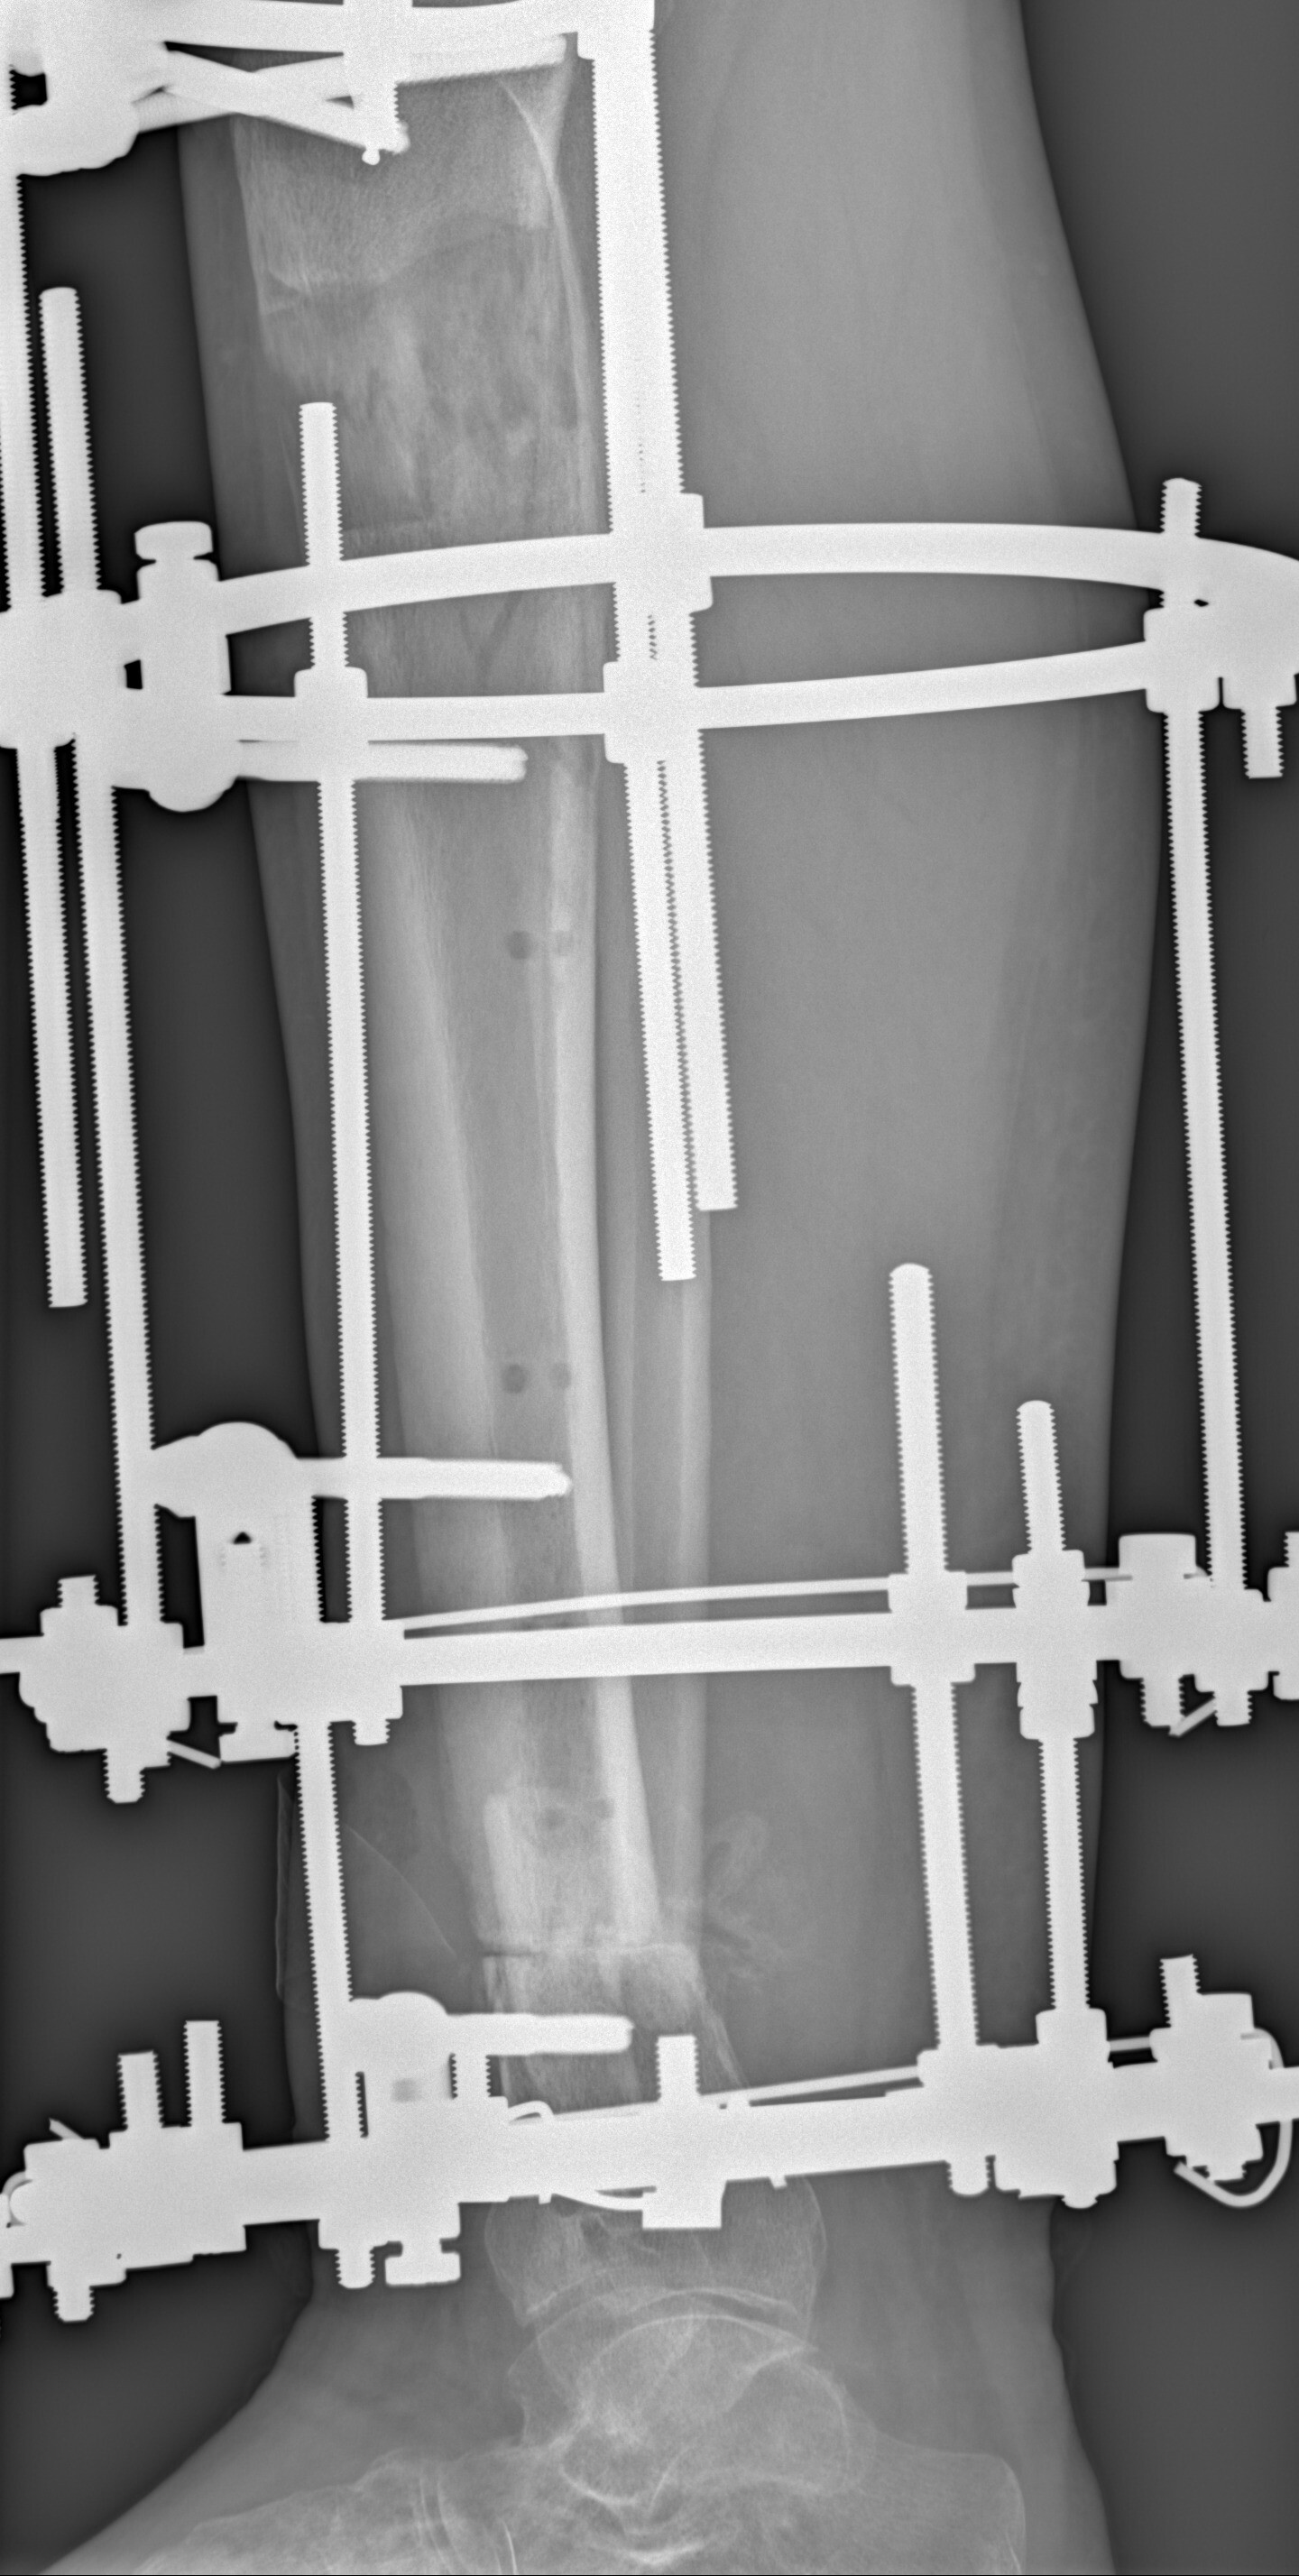

Дома стало гораздо лучше. Перевязываюсь каждый день. Язва уменьшилась. Нога потихоньку перестала болеть. Сначала таблетка обезболивания начинала мой день, в течение месяца стал пить пару раз в неделю, когда нужно куда-то далеко идти (в суд, например). Примерно через месяц я стал ходить с одним костылем и нагружать ногу. Сначала на обезболивающем, опираясь на стенку и предметы мебели. Потом и просто так. И вот, совсем недавно, я осмелел и стал ходить совсем без костылей. Пока по квартире. Вот такие достижения н сегодняшний день. На контрольных рентгенах вверху нарастает регенерат, внизу начинает формироваться костная мозоль, ещё незначительно, но вроде признаки есть